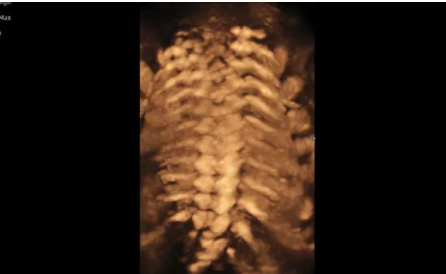

3D/4D成像方面,Hera i 10通過結(jié)合先進(jìn)的圖像渲染技術(shù),著重加強了邊緣和小結(jié)構(gòu)的可視化能力。